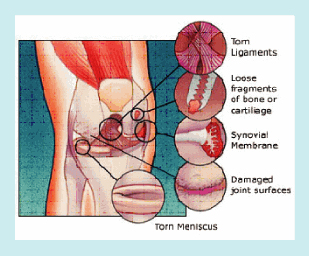

การเปลี่ยนแปลงของข้อ

- กระดูกอ่อนผิวข้อ มีการนุ่มลง เมื่อเป็นมากขึ้นกระดูกอ่อนผิวข้อก็อาจจะหายไปเลยทำให้กระดูกของข้อมาถูกันถ้าการสึกหรอของกระดูกอ่อนผิวข้อไม่เท่ากัน ก็จะทำให้กระดูกทรุดเข้าหากัน และทำให้เกิดมีแนวของข้อผิดไป เกิดขาโก่งหรือขาเกขึ้นได้

- การกระจายการรับน้ำหนักของกระดูกผิวข้อ ผิดปกติ ทำให้การรับน้ำหนักผิดปกติ

- เยื่อหุ้มข้อ ถูกระคายเคือง เกิดการอักเสบ และสร้างน้ำในข้อมากขึ้น ทำให้เกิดอาการปวด บวม และข้ออุ่น

- กล้ามเนื้อรอบข้อเข่า มีความแข็งแรงน้อยลง แรงกระแทกจึงเกิดกับผิวข้อมากขึ้น

- เอ็นยึดข้อ บางส่วนหย่อนยานขึ้น ทำให้ข้อแกว่ง หรือหลวมมากขึ้น

- กระดูก มีการหนาตัวของกระดูก และบริเวณขอบของกระดูกจะเห็นกระดูกงอก

รูปภาพแสดง การเปลี่ยนแปลงของข้อเข่าเสื่อม

สิ่งต่าง ๆ ที่เกิดขึ้นเหล่านี้ล้วนเป็นเหตุเป็นผลซึ่งกันและกัน ในระยะแรก ผู้ป่วยมักมีข้อเข่าบวม อาจร่วมกับอาการปวด อาการขัดที่ข้อ โดยอาการจะเป็นมากขึ้นเมื่อมีการเคลื่อนไหว คือในขณะเหยียดและงอข้อเข่า ซึ่งเกิดจากการที่กระดูกอ่อนผิวข้อไม่เรียบและมีกระดูกงอกเกิดขึ้น ผู้ป่วยบางคนก็จะปรับตัวด้วยการไม่เหยียด หรืองอข้อเข่า เมื่อเวลาผ่านไป ทำให้เกิดปัญหาข้อติดขัดตามมา อาการเหล่านี้จะเป็นมากขึ้นเมื่อเวลาผ่านไป ขณะเดียวกันถ้าข้อที่เสื่อมอักเสบนั้นถูกใช้งานมากและต่อเนื่องอาการก็จะเป็นมากขึ้นได้เช่นกัน